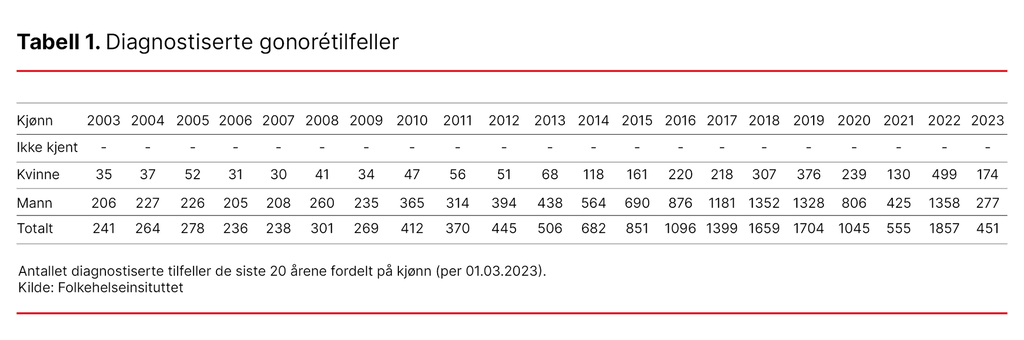

Gonoré er på fremmarsj i Norge. Hvis utviklingen fortsetter, ligger det an til mer enn 3000 gonorétilfeller i 2023, hvorav 1000 tilfeller blant kvinner.

Økningen skyldtes trolig redusert bruk av kondom på grunn av mindre frykt for hiv. Under covid-pandemien sank forekomsten, men nå ringer alarmklokkene på nytt. Gonoré er på fremmarsj igjen, og denne gangen spesielt blant unge kvinner. I starten av mars 2023 er antall smittede kvinner nesten fem ganger så høyt som det totale antall smittede kvinner i hele 2003. Og russetiden har ikke engang begynt (se tabell 1) (5).

Nå står våren og sommeren for tur med russetid, økt reiseaktivitet og fadderukene. Hvis utviklingen fortsetter, kan vi få over 3000 gonorétilfeller totalt og over 1000 tilfeller blant kvinner i 2023 (12).